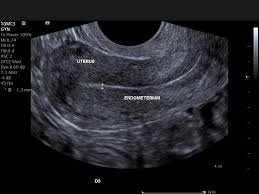

- Follicular Monitoring: Tracks the growth of egg-containing follicles and measures endometrial thickness (uterine lining) to determine the best time for ovulation, IUI, or egg retrieval.

TVS (Transvaginal Sonography)

An ultrasound where a probe is inserted into the vagina to get clear images of pelvic organs.